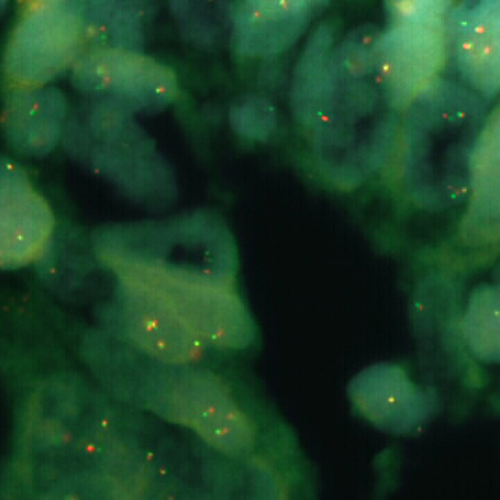

Diffuse Large B-Cell Lymphoma stained using Kreatech MYC (8q24) Break

XL probe for BOND (KBI-XL006).

MYC (8q24) Break - XL for BOND FISH probe detects genomic translocations involving the MYC gene. MYC (8q24) Proximal - XL and MYC (8q24) Distal - XL are optimized to detect the genomic regions proximal and distal to break points in the MYC gene region. When combined, both probes are used to detect translocations involving the MYC gene at 8q24.